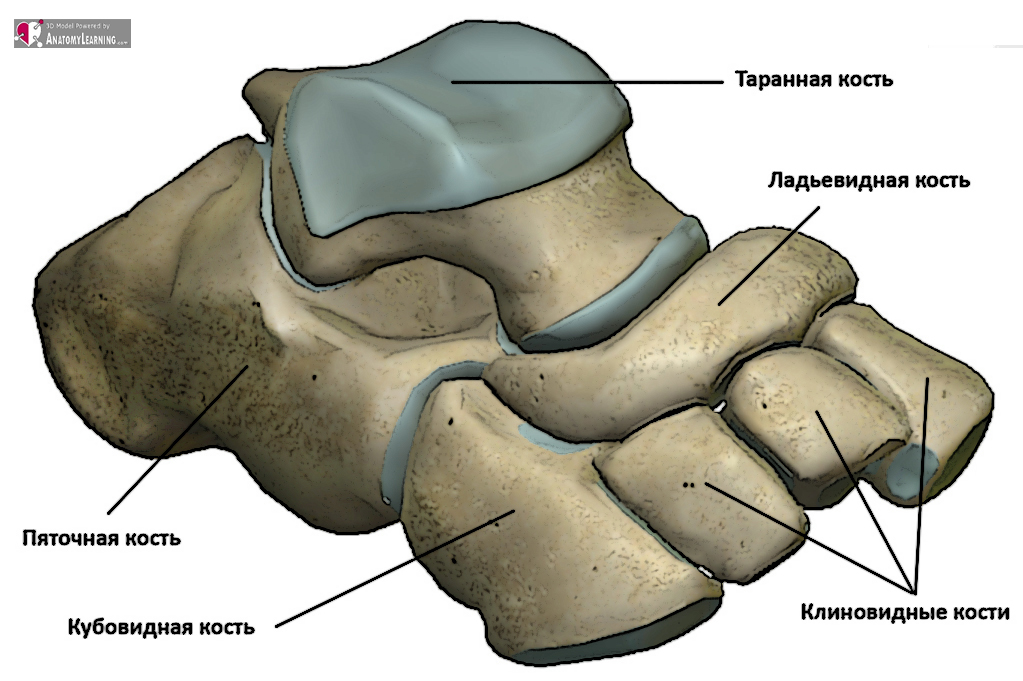

Анатомические фото голеностопного сустава и его суставных поверхностей